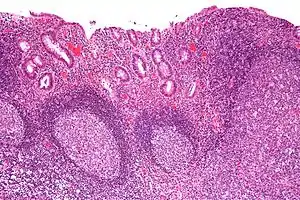

Diversion colitis is an inflammation of the colon which can occur as a complication of ileostomy or colostomy, where symptoms may occur between one month and three years following surgery.[1] It also occurs frequently in a neovagina created by colovaginoplasty, with varying delay after the original procedure.[2] Despite the presence of a variable degree of inflammation the most suggestive histological feature remains the prominent lymphoid aggregates.

| Micrograph showing colonic-type mucosa with follicular lymphoid hyperplasia, as is seen in diversion colitis. H&E stain. | |